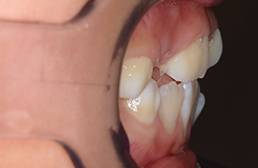

| 主訴 | 上顎前歯のでこぼこ | 診断名 | アングルⅡ級叢生症例 | ||||

|---|---|---|---|---|---|---|---|

| 初診時年齢 | 6歳9ヵ月 | 性別 | 男 | 動的治療期間 | 6ヵ月 | ||

| 既往歴として上顎正中過剰歯(2本)は抜去済み。その影響で上顎右側中切歯は捻転して萌出しており、下顎右側中切歯と早期接触が認められたため2x4(上顎のみブラケット装着)にて前歯部の改善を行った。現在は永久歯列完成まで経過観察を行い、希望があれば口元の突出感を改善するために本格矯正治療を行うことにしている。 | |

| セファロ所見 | 上下顎骨は調和のとれた位置関係を示していたが、頭蓋に対して両顎共に前方に位置していた。上下顎前歯は唇側傾斜していた。 |